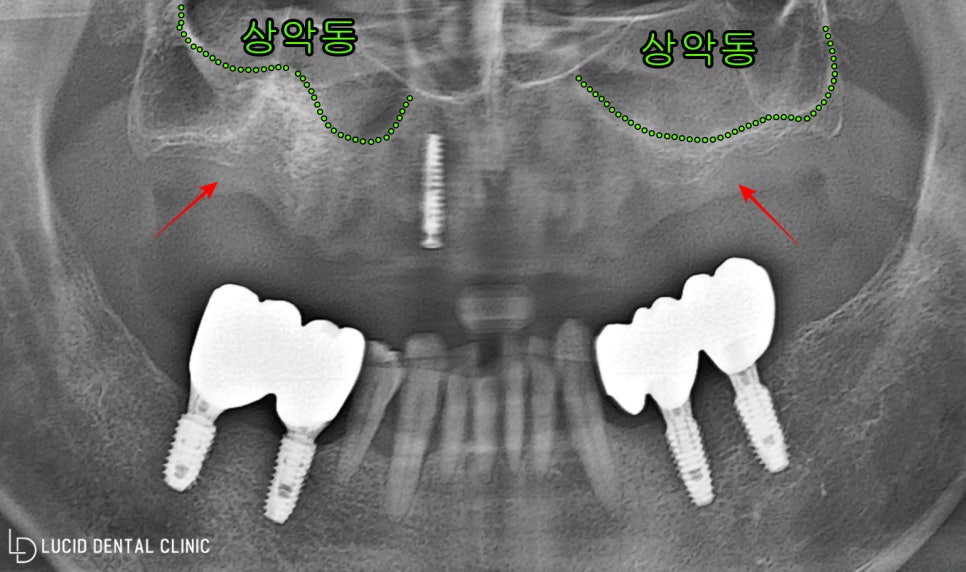

아래와 같이 엑스레이를 통해

전체 구강 환경을 살펴본 결과,

위턱 치아를 모두 잃은 채,

픽스처 하나가 식립된 모습을

발견할 수 있었습니다.

자세히 여쭤 보니 타원에서 받은 것으로,

마음에 들지 않아 본원에 오셨다는데요

현재 위턱 주변에 위치하고 있는

상악동과 근접하게 뼈가 소실되어,

발치한 시간이 오래되었다는

사실까지 추측할 수 있었습니다.

이런 환경에서 임플란트

수술 을 진행하게 될 경우,

픽스처를 단단히 고정하지 못하고

해부학 구조에 천공이 나타날 수 있어

미리 CT 사진으로 분석한 다음,

상악동을 들어 올리는

골이식 과정을 병행해야 됩니다.